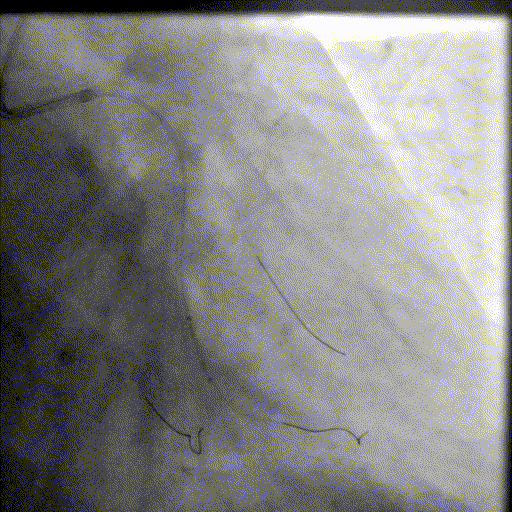

LAD处理:

球囊预扩

用预扩球囊扩张LAD病变,支架无法通过。为了解血管病变分布情况及钙化程度,遂启用IVUS检查。

术前腔内影像学IVUS指导

IVUS提示LAD近中段钙化病变,中段可见360°环形钙化。

冲击波球囊治疗

3.0x12@4atm 冠脉血管内冲击波导管顺利推送至前降支近端,但无法通过成角钙化处,故于血管近端就地进行10个周期治疗,复查造影见近端狭窄明显减轻;再次选择2.5x12@4atm冠脉血管内冲击波导管推送至成角钙化处,逐步掘进扩张病变并给予冲击波治疗,最终顺利通过成角钙化处,并于前降支中段再次进行10个周期的冲击波治疗。

支架植入并后扩

于LAD近中段串联植入两枚药物洗脱支架,经非顺应性球囊后扩张支架,复查造影及IVUS提示支架膨胀完全,贴壁良好,无夹层撕裂。